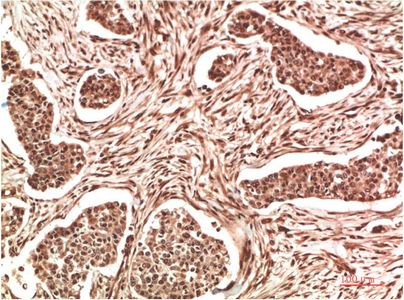

Main InformationTargetNM23-H1Host SpeciesRabbitReactivityHuman, Rat, MouseApplicationsIHC, IFMW17kD (Observed)Conjugate/ModificationUnmodifiedDetailed InformationRecommended Dilution RatioIHC 1:100-200; IF 1:50-200FormulationLiquid in PBS containing 50% glycerol, 0.5% BSA and 0.02% sodium azide.SpecificityNM23A protein detects endogenous levels of NME1PurificationThe antibody was affinity-purified from rabbit antiserum by affinity-chromatography using epitope-specific immunogen.Storage-15°C to -25°C/1 year(Do not lower than -25°C)Concentration1 mg/mlMW(Observed)17kDModificationUnmodifiedClonalityPolyclonalIsotypeIgGAntigen&Target InformationImmunogen:Recombinant Protein of NM23A of NME1Specificity:NM23A protein detects endogenous levels of NME1Gene Name:NME1Protein Name:NME1Other Name:NME1Background:This gene (NME1) was identified because of its reduced mRNA transcript levels in highly metastatic cells. Nucleoside diphosphate kinase (NDK) exists as a hexamer composed of 'A' (encoded by this gene) and 'B' (encoded by NME2) isoforms. Mutations in this gene have been identified in aggressive neuroblastomas. Two transcript variants encoding different isoforms have been found for this gene. Co-transcription of this gene and the neighboring downstream gene (NME2) generates naturally-occurring transcripts (NME1-NME2), which encodes a fusion protein comprised of sequence sharing identity with each individual gene product. [provided by RefSeq, Jul 2008],Function:Catalytic activity:ATP + nucleoside diphosphate = ADP + nucleoside triphosphate.,cofactor:Magnesium.,Disease:This protein is found in reduced amount in tumor cells of high metastatic potential.,Disease:This protein is found in reduced amount in tumor cells of high metastatic potential. Somatic mutations of NME1 are found in neuroblastoma. Increased NME1 in neuroblastoma is correlated with features of the disease that are associated with aggressive tumors. May therefore have distinct if not opposite roles in different tumors.,enzyme regulation:Autophosphorylation at His-118 increases serine/threonine protein kinase activity of the enzyme. Interaction with the SET complex inhibits exonuclease activity.,Function:Major role in the synthesis of nucleoside triphosphates other than ATP. Negatively regulates Rho activity by interacting with AKAP13/LBC. Acts as a transcriptional activator of the c-Myc gene; binds DNA non-specifically (PubMed:8392752).,Function:Major role in the synthesis of nucleoside triphosphates other than ATP. Possesses nucleoside-diphosphate kinase, serine/threonine-specific protein kinase, geranyl and farnesyl pyrophosphate kinase, histidine protein kinase and 3'-5' exonuclease activities. Involved in cell proliferation, differentiation and development, signal transduction, G protein-coupled receptor endocytosis, and gene expression. Required for neural development including neural patterning and cell fate determination. Has tumor metastasis-suppressive capacity.,PTM:The N-terminus is blocked.,similarity:Belongs to the NDK family.,subcellular location:Cell-cycle dependent nuclear localization which can be induced by interaction with Epstein-barr viral proteins or by degradation of the SET complex by GzmA.,subcellular location:Isoform 2 is mainly cytoplasmic and isoform 1 and isoform 2 are excluded from the nucleolus.,subunit:Hexamer of two different chains: A and B (A6, A5B, A4B2, A3B3, A2B4, AB5, B6). Interacts with CAPN8 (By similarity). Interacts with AKAP13.,subunit:Hexamer of two different chains: A and B (A6, A5B, A4B2, A3B3, A2B4, AB5, B6). Interacts with SET and PRUNE.,tissue specificity:Isoform 1 is expressed in heart, brain, placenta, lung, liver, skeletal muscle, pancreas, spleen and thymus. Expressed in lung carcinoma cell lines but not in normal lung tissues. Isoform 2 is ubiquitously expressed and its expression is also related to tumor differentiation. Isoform 3 is ubiquitously expressed.,tissue specificity:Ubiquitously expressed.,Cellular Localization:Cytoplasm . Nucleus . Cell-cycle dependent nuclear localization which can be induced by interaction with Epstein-barr viral proteins or by degradation of the SET complex by GzmA.Tissue Expression:Isoform 1 is expressed in heart, brain, placenta, lung, liver, skeletal muscle, pancreas, spleen and thymus. Expressed in lung carcinoma cell lines but not in normal lung tissues. Isoform 2 is ubiquitously expressed and its expression is also related to tumor differentiation.Research Areas:>>Purine metabolism ; >>Pyrimidine metabolism ; >>Drug metabolism - other enzymes ; >>Metabolic pathways ; >>Nucleotide metabolism ; >>Biosynthesis of cofactors